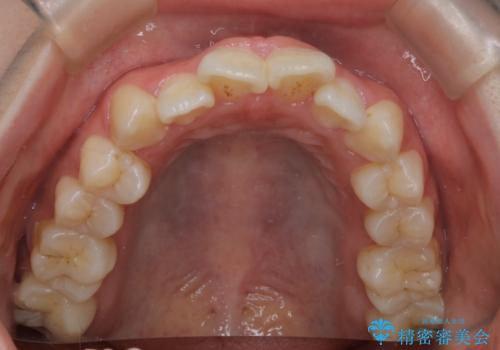

【インビザライン】マウスピースで開咬改善

- 開咬を主訴に来院されました。

IPR(歯と歯の間を削る処置)と顎間ゴムを行いながら、インビザラインで開咬を治療する計画を立てました。

治療をしながら、MFT(口腔筋機能療法)も行っていくことにしました。

歯の移動量が多いケースでしたが、患者様にマウスピースの使用とゴム掛けを頑張っていただいたので

リファイメント1回のみで治療を終わることができました。